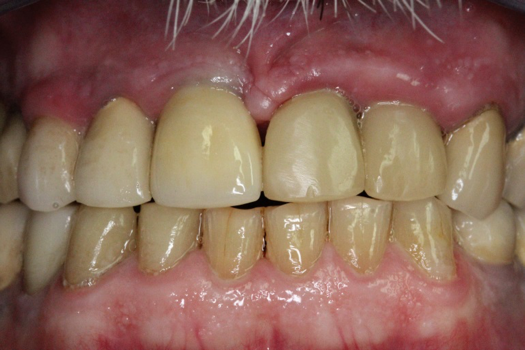

After 4 months of healing and integration of the bone around the implant, the digital workflow was initiated to develop the abutment and treatment plan. Another analog impression was made with an impression post and polyvinyl impression. The laboratory scanned the impression and digitized it to create the emergence profile of the milled titanium abutment and the final restoration (Figure 10 and Figure 11). The patient had a considerably thick soft-tissue profile, allowing a milled titanium abutment. The decision to use a titanium abutment was based on the patient's occlusion and propensity to fracture teeth or restorations. The virtual model was gray because the scanner does not recognize the color of the analog impression. The virtual final abutment and crown were approved and fabrication completed. The final restoration met the patient's esthetic values and his ability to function (Figure 12 and Figure 13).

Fig 12. Six months after cementation.

Figure 12